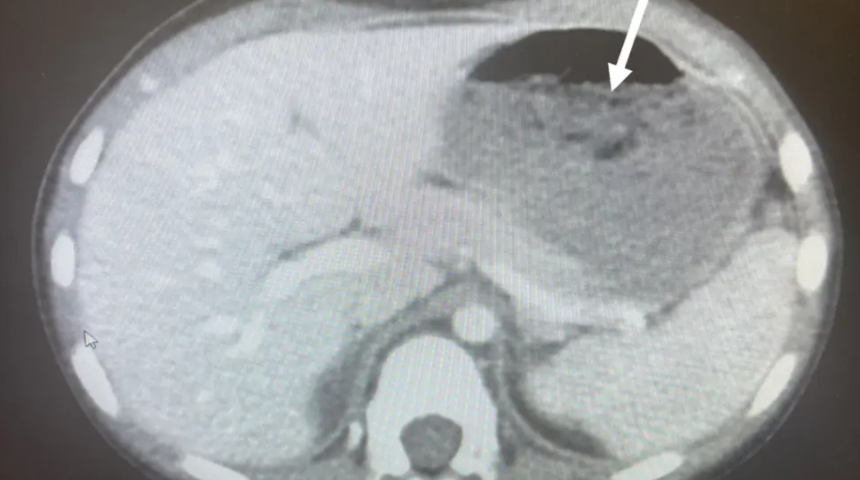

Hastanede yapılan incelemelerin sonucunda küçük çocuğun midesinin dörtte birini kaplayan büyük bir sakız yumağı keşfedildi. Doktorlar röntgen sonuçlarının ardından küçük çocuğu ameliyata alarak sindirim sistemini tıkayan sakız yumağını çıkarttı. Doktorlar sakız yumağını çıkartmak için küçük çocuğun boğazından aşağı bir özofagoskop ile metal bir tüp yerleştirdi.